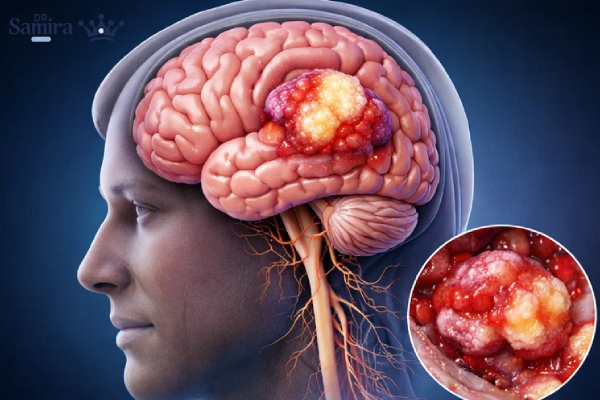

گانگلیوگلیوما (Ganglioglioma) نوعی تومور مغزی نادر است که از ترکیب دو نوع سلول تشکیل میشود: سلولهای نورونی بالغ و سلولهای گلیال نئوپلاستیک. این ترکیب باعث میشود که گانگلیوگلیوما در گروه تومورهای نورونال گلیال قرار بگیرد. بر اساس طبقهبندی سازمان جهانی بهداشت (WHO)، این تومور اغلب در دسته تومورهای درجه I قرار دارد و رفتار نسبتاً خوشخیمی از خود نشان میدهد. با این حال، در موارد نادر ممکن است دچار تغییرات بدخیم شود.

شایعترین محل درگیری این تومورها لوب تمپورال مغز است؛ ناحیهای که نقش مهمی در حافظه و بروز تشنج دارد. به همین دلیل، بسیاری از بیماران مبتلا به گانگلیوگلیوما یا گانگلیوسیتوما با صرع لوب تمپورال مراجعه میکنند. این تومورها همچنین میتوانند در لوبهای فرونتال، پاریتال، مخچه و بهندرت در ساقه مغز یا نخاع مشاهده شوند.

تشخیص این تومورها اصولا با استفاده از MRI مغز انجام میشود. در تصویربرداری، گانگلیوگلیوما اغلب بهصورت ضایعهای با حدود نسبتا مشخص و ترکیبی از بخشهای کیستیک و جامد دیده میشود. در تصاویر T2 و FLAIR افزایش سیگنال مشاهده میشود و میزان جذب ماده حاجب متغیر است. در CT scan، وجود کلسیفیکاسیون نسبتاً شایع است. تشخیص قطعی تنها با بررسی پاتولوژیک و ایمونوهیستوشیمی امکانپذیر است.